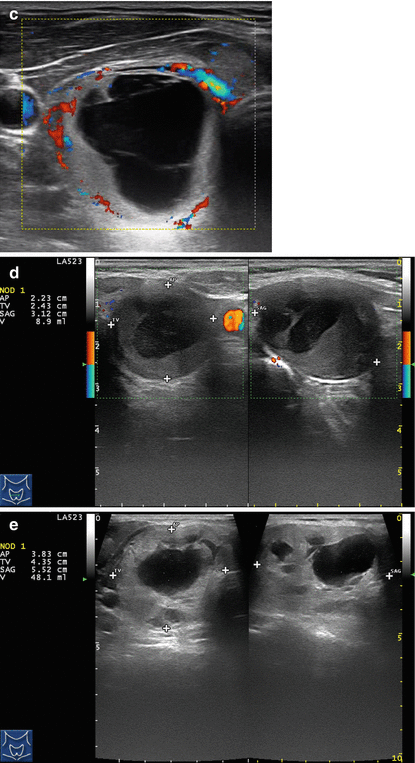

Facial pain info, trigeminal neuralgia is an inflammation of the trigeminal nerve causing extreme pain and muscle spasms in the face . . . . Glycerol injection provides immediate pain relief in 70% of patients [2] . About 50% of patients experience pain recurrence within 3 to 4 years . . . . In glycerol injection, alcohol (green) damages nerve fibers . . .